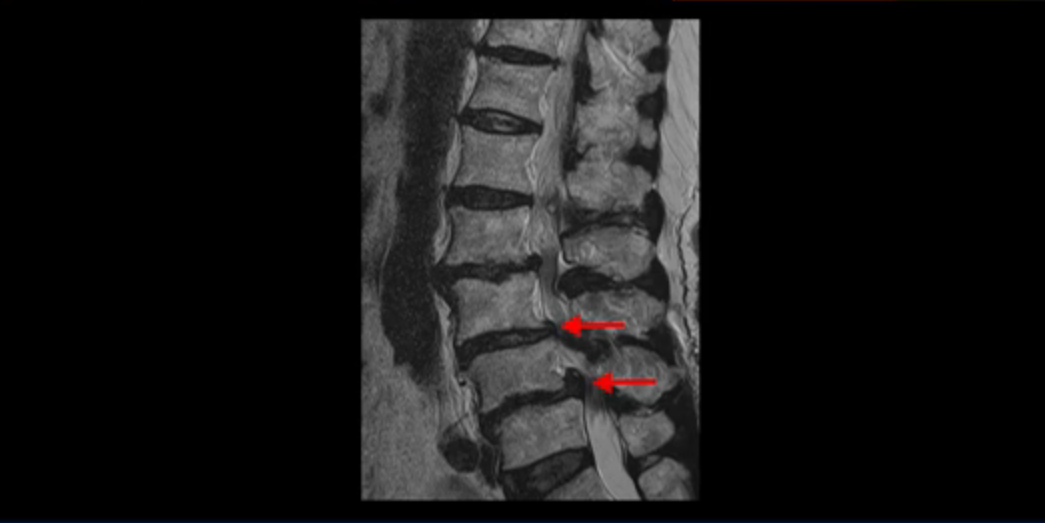

이 환자분 MRI를 보면서 더 자세히 설명 드리겠습니다. 이분은 허리의 다섯 마디가 다 안 좋은 환자분입니다. 84세 고령의 나이에 이렇게 여러 마디가 안 좋으면 대학병원에서도 수술이 어렵다는 얘기를 듣는 경우가 많습니다. 또 수술을 하더라도 결과가 안 좋을 수 있다는 얘기를 들을 가능성이 높습니다.

보시다시피 허리 다섯 마디 전부가 다 퇴행되어 있고,

두 마디에 전방전위증이 있고,

2번 3번,

3번 4번,

4번 5번에 중심성 협착이 심하고

거의 모든 추간공 즉, 신경가지가 좌우로 빠져나가는 구멍이 다 좁아져 있습니다.